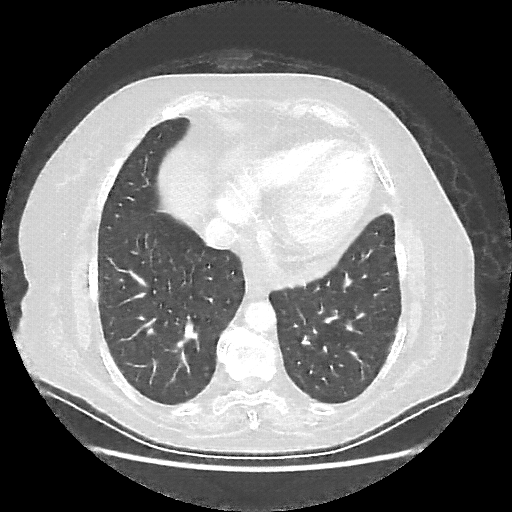

Targeted Slice 70 - Lung Window Analysis (Generated vs Real Venous)

0.747

Lung SSIM

92.5

Lung RMSE

41.3

Lung MAE

Average Lung Window Metrics Across All Slices (101 slices) - Generated vs Real Venous

0.731

Lung SSIM (Avg)

82.0

Lung RMSE (Avg)

39.1

Lung MAE (Avg)

Reconstructed NATIVE CT scan (cycle consistency)

Lung window (WL -600, WW 1500 β†’ Low βˆ’1350, High +150)

Generated VENOUS CT scan (A→B translation)